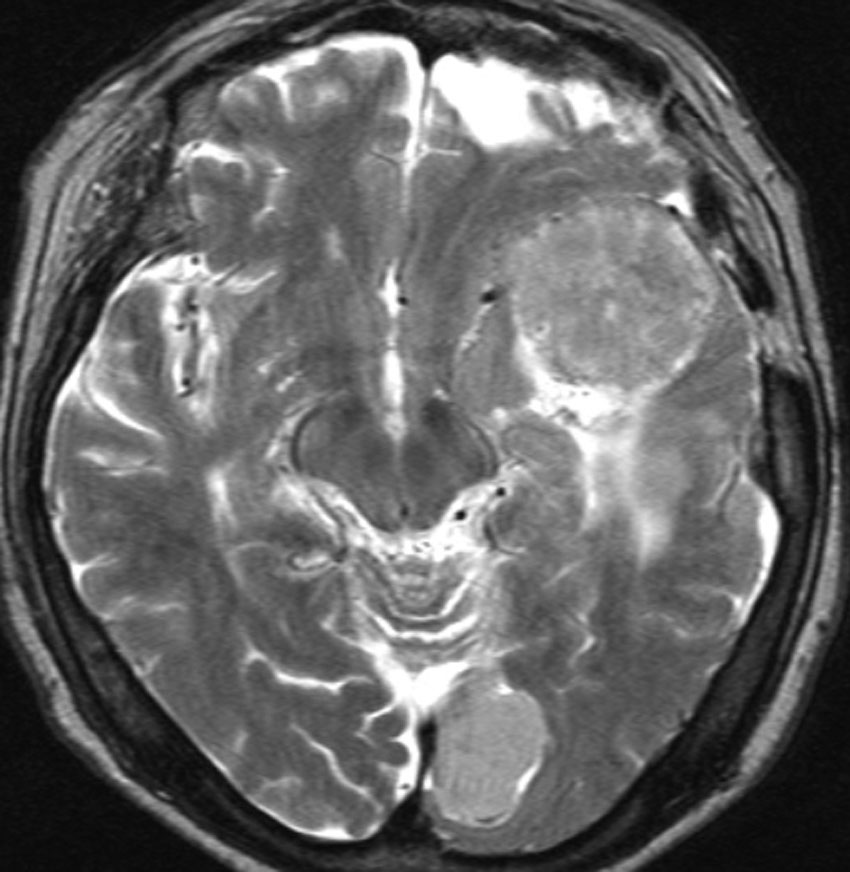

全髄膜の腫瘍化,NF-2

テント下を含めて頭蓋内の全ての髄膜が同時に腫瘍化してきます。この患者さんはNF-2なのですが,NF-2がない患者さんにもmeningiomatosisはあります。脳圧亢進による視神経乳頭萎縮で両側の視力が無くなるというような症状が出ます。これは手術適応がないタイプです。